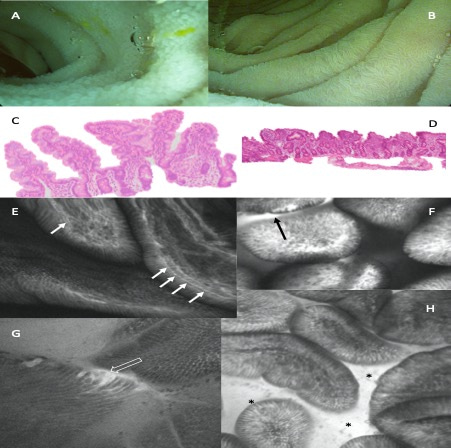

Worldwide, 5.6 million children die before their firth birthday each year, with 80% of these deaths occurring in sub-Saharan Africa and Asia. Almost half of these deaths occur in children with malnutrition and it has been suggested that this may be due to an elevated susceptibility to life threatening infections. In Zambia, 35% of our children are stunted, 4% are wasted and 12% are underweight. Our research team has carried out malnutrition-related work in a disadvantaged community for over two decades and have found that enteropathy, a subclinical condition that is defined by alterations in mucosal structure and function is almost universally present in children with malnutrition (Figure 1). Repeated enteropathogen exposure also contributes to growth failure resulting from epithelial damage and consequent microbial translocation.

Figure 1: The presence of environmental enteropathy evidenced by blunted villi (A-D) and epithelial fluorescein leakage (E-H)